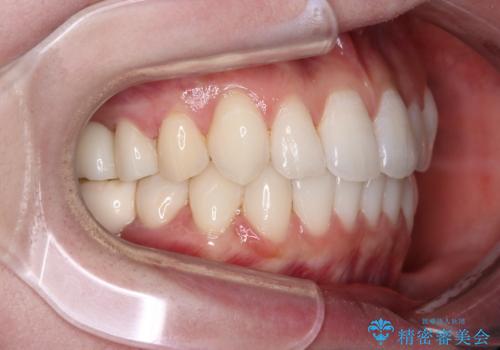

- 2、3年後にワーキングホリデーで海外に行くため、その前に歯列やむし歯をきれいにしたいとのことで来院された患者様です。

抜歯の必要な右上の奥歯は事前に抜歯をし、インビザラインにて上下歯列を整えることとしました。

矯正治療後半に奥歯の補綴治療が必要な歯にはオールセラミッククラウンを装着し、インビザラインで最終的に仕上げることとしました。

海外に行く前に口腔内環境を整えることができ、患者様には大変満足していただきました。